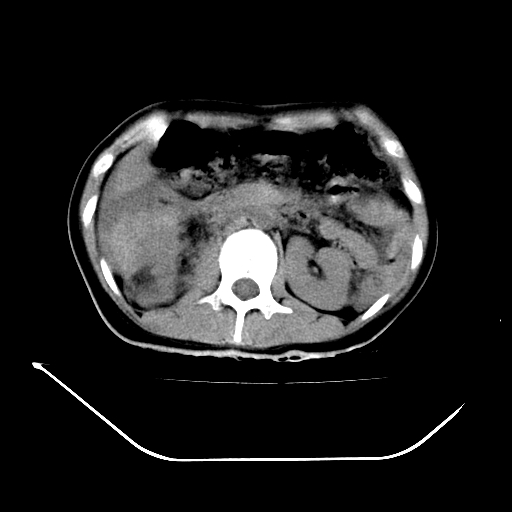

以下是引用liuyue在2008-7-19 13:02:00的发言:[br]1.肝右叶后下段及右肾挫裂伤伴腹腔积血。[br]2.右侧多发性肋骨骨折、横突骨折、右髂骨骨折伴周围软组织挫伤。[br]3.右侧腰大肌肿胀,并可见低密度影,如为气体,则肠道挫裂伤待除外。

以下是引用zhengfaming在2008-7-19 14:42:00的发言:[br]1.肝右叶后下段及右肾挫裂伤伴腹腔积血。脾脏挫裂伤待排[br]2.右侧多发性肋骨骨折、横突骨折、右髂骨骨折伴周围软组织挫伤。[br]3.右侧腰大肌肿胀,并可见低密度影,如为气体,则肠道挫裂伤待除外

以下是引用道哥在2008-7-19 16:52:00的发言:[br]肝右叶后下段及右肾挫裂伤、脾破裂伴腹腔积血。[br]2.双侧多发性肋骨骨折、横突骨折、右髂骨骨折伴周围软组织挫伤。[br]3.右侧腰大肌肿胀,并可见低密度影,如为气体,则肠道挫裂伤待除外。